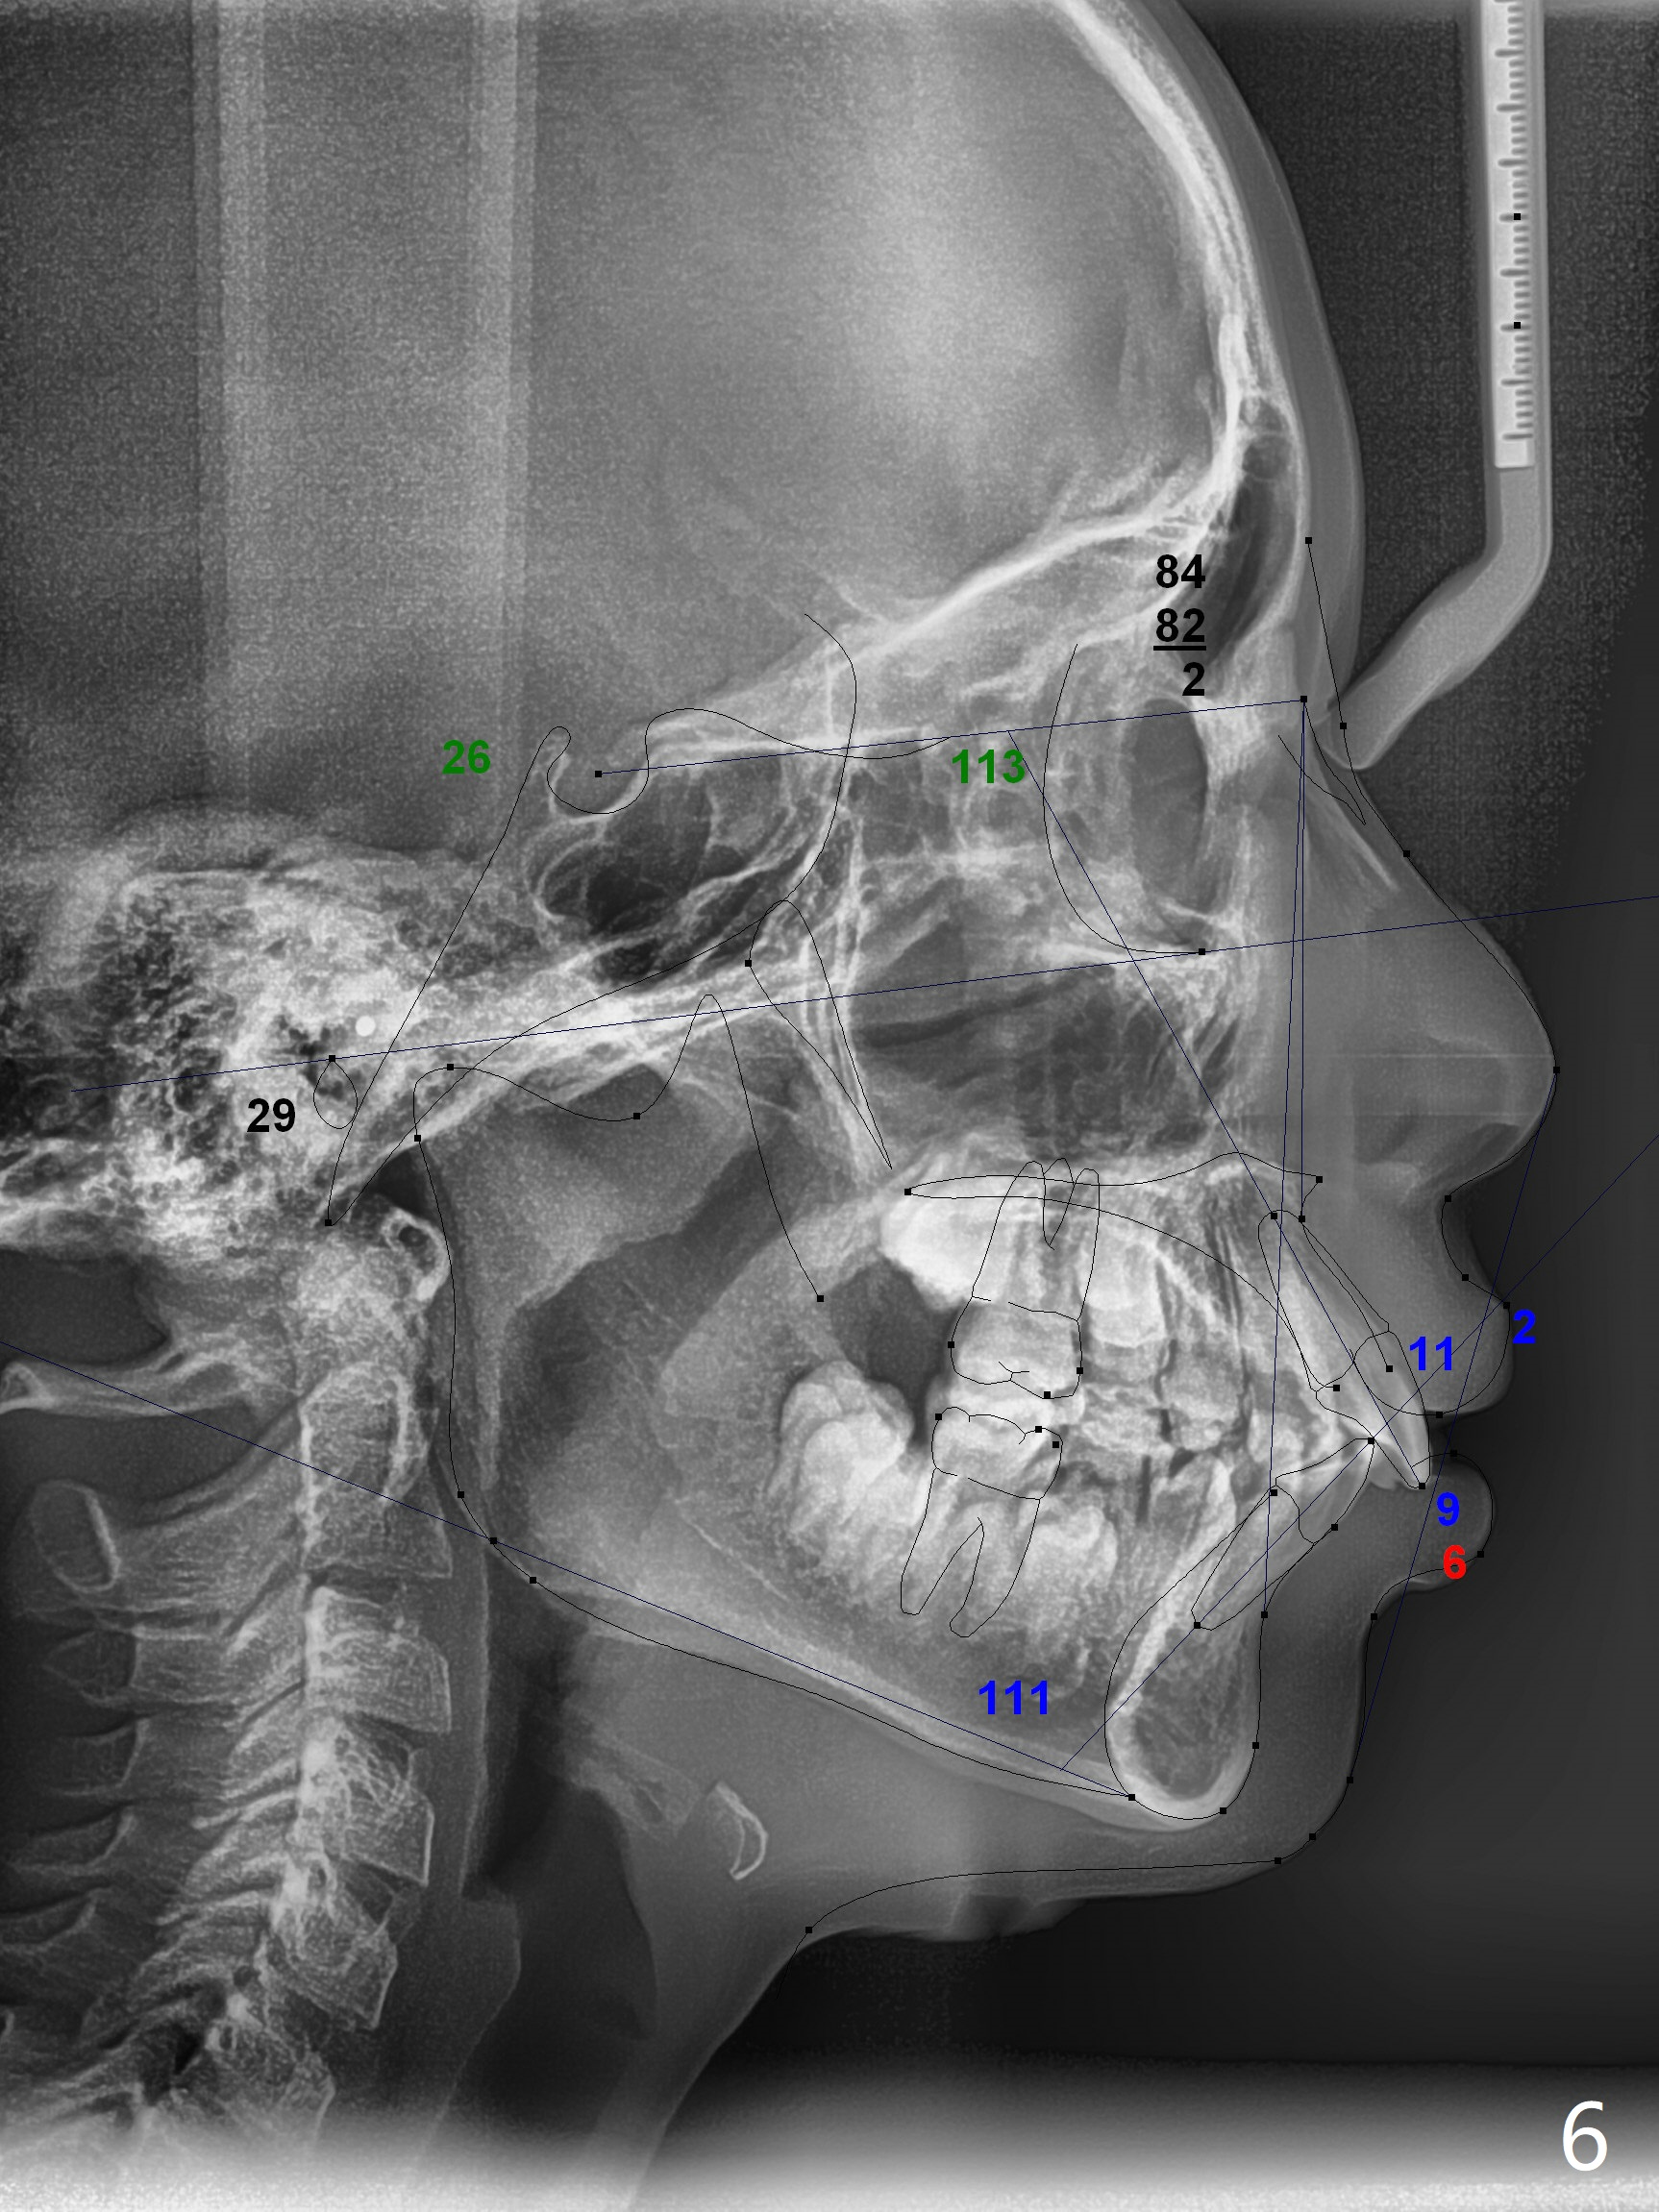

The mother of a 10-year-7-month old man requests treatment for the crowding lower incisors (Fig.14). The canines and molars are Class II by a half of a tooth (Fig.7,9,10,12). The dentition is mixed with E retention (Fig.13,14,16). Orthodontic treatment will start before E exfoliation for alignment and establishment of Class I occlusion as much as possible by distalizing U6s. Fine adjustment for intedigitation will be made when E exfoliate.